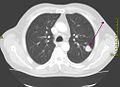

-

CT-Thoraxaufnahme (axiales Schnittbild)